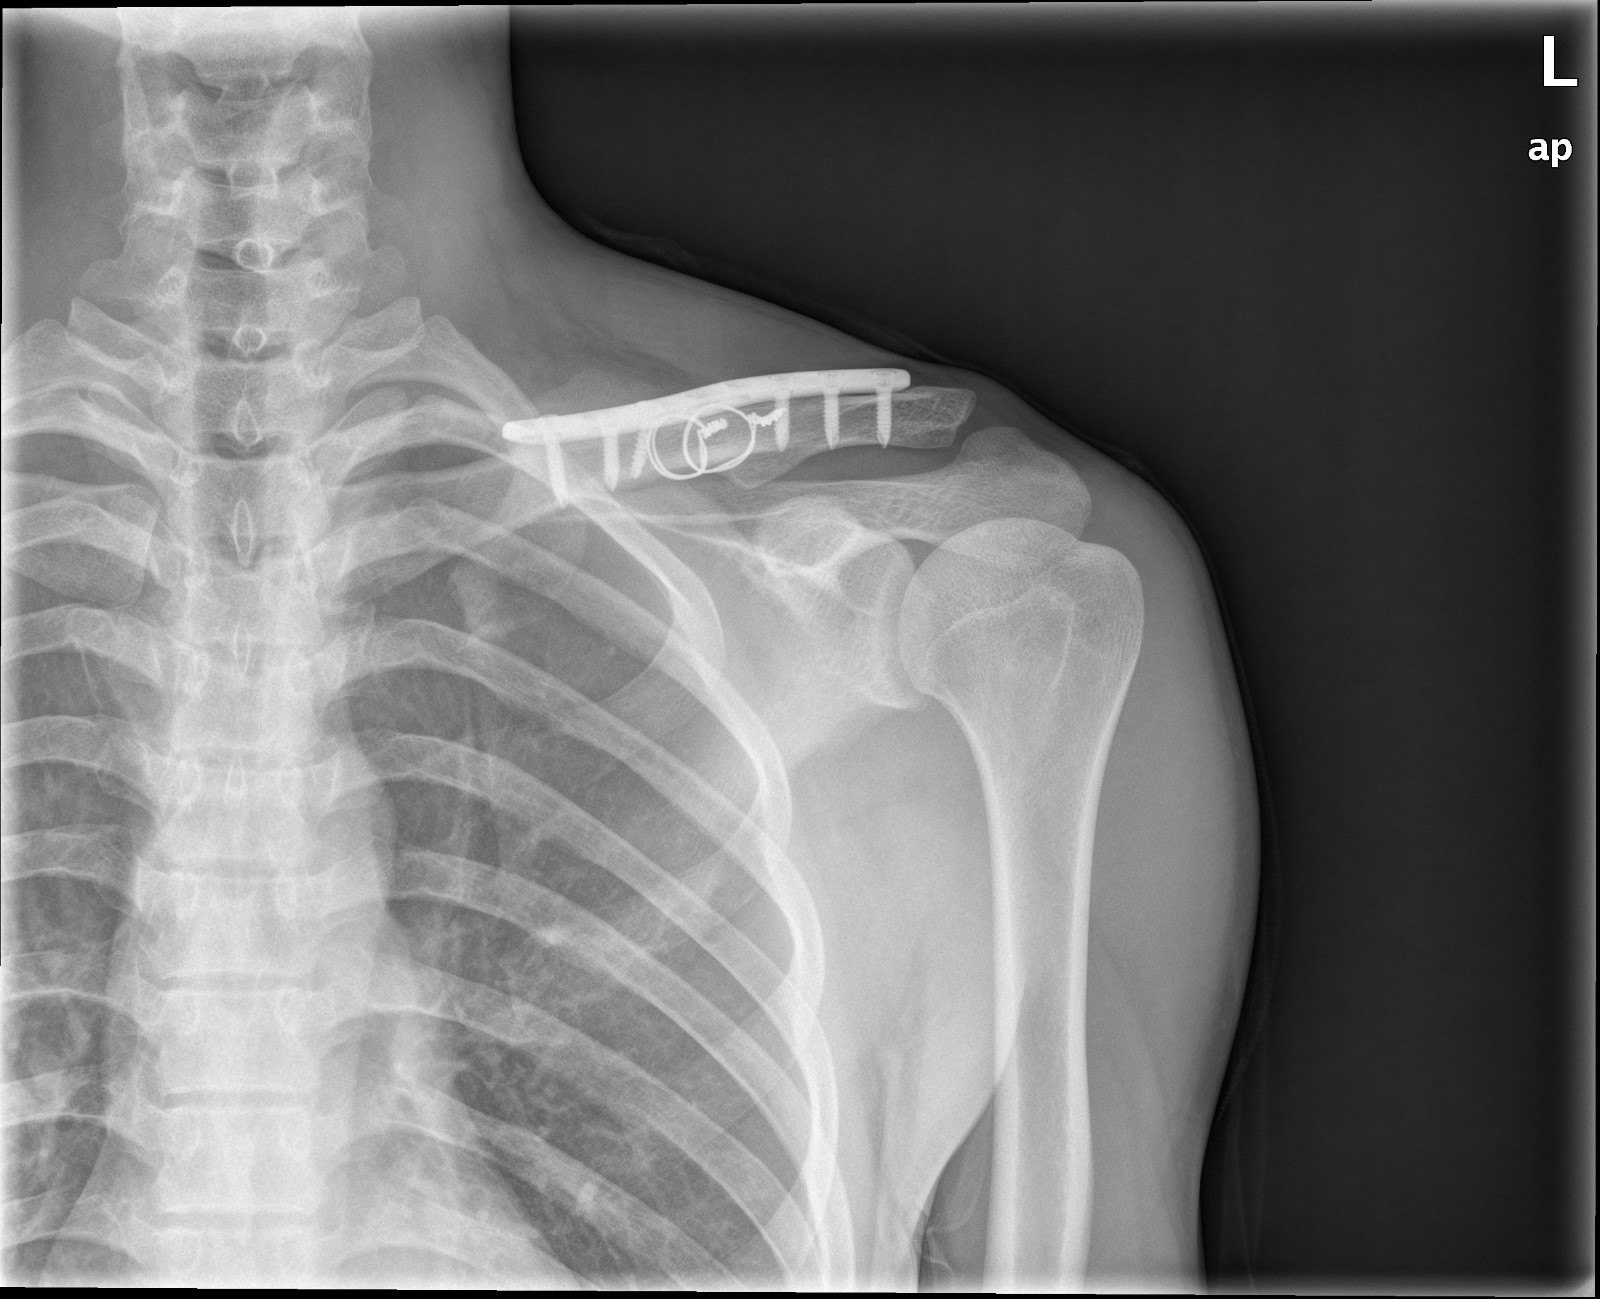

解剖螺旋型互鎖式鋼板鎖骨骨折治療新利器 Ettoday健康雲 Ettoday新聞雲

微創手術治療鎖骨骨折效果佳 Coolanews府城電子報 Pchome 個人新聞台

まあ、今回の鎖骨プレート除去(抜釘)手術は埋め込む時の手術後よりも大分楽でした。 入院期間もプレートを埋め込んだ時は3泊4日で5日間の入院期間を要しましたが、今回は 2日間の入院 で済みました。 入院となると費用の方が気になりますよね。鎖骨骨折をしたら知っておいて欲しいこと 鎖骨バンドは二枚以上必要 鎖骨を骨折して、病院に行くと 鎖骨バンド と呼ばれるものを処方されます。 手術をするほどの怪我の場合はされないことがあります。Mixi鎖骨骨折者 骨が付くまでの期間は 折れかたによって違うのでしょうか? 自分はズレがほとんどないらしいのですが、その方が早く治ったりするのでしょうか? 年齢によっても違うと聞きましたが、みなさんは何歳ぐらいで、どれくらいの怪我でどれくら